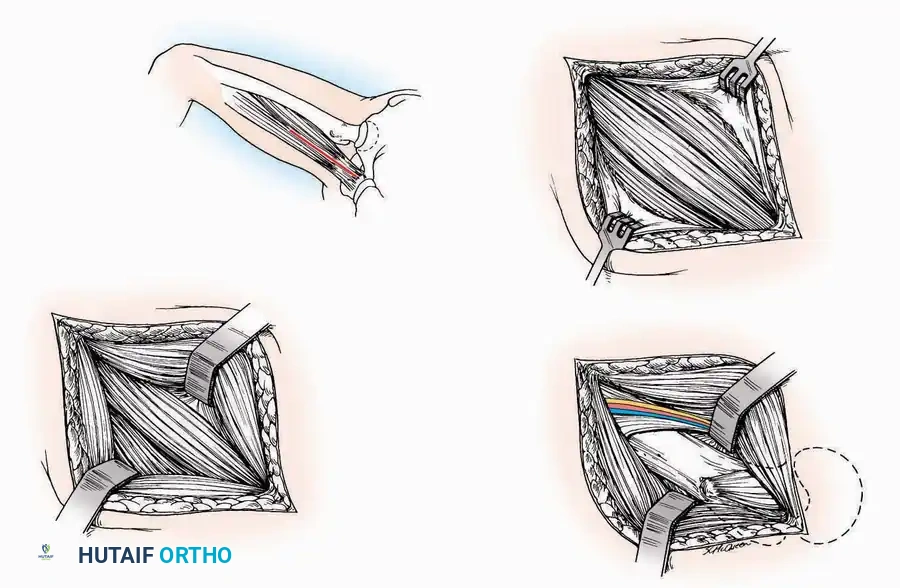

Anterior Approach

Indications: Total ankle arthroplasty (TAA), anterior ankle arthrodesis, and excision of anterior tibial/talar osteophytes (anterior impingement).

💡 Clinical Pearl

Gaining access to the medial gutter (the articulation between the medial malleolus and the medial articular facet of the talus) can be challenging through a pure anterior approach. Meticulous medial subperiosteal dissection of the joint capsule is required to avoid excessive traction on the anterior neurovascular bundle.

Surgical Technique:

* Incision: Make a 10 to 15 cm longitudinal incision over the anterior aspect of the ankle, centered exactly midway between the medial and lateral malleoli.

* Superficial Dissection: Incise the superficial fascia. Identify and protect the superficial peroneal nerve branches laterally and the saphenous nerve medially.

* Internervous Plane: The deep dissection exploits the plane between the Extensor Hallucis Longus (EHL) tendon (innervated by the deep peroneal nerve) and the Extensor Digitorum Longus (EDL) tendons (also innervated by the deep peroneal nerve).

* Neurovascular Bundle: Incise the extensor retinaculum. Carefully identify the anterior tibial artery and the deep peroneal nerve, which typically lie between the EHL and EDL, or directly deep to the EHL. Retract the neurovascular bundle laterally with the EDL, or medially with the EHL, depending on the specific anatomical variant encountered (lateral retraction is most common).

* Capsulotomy: Incise the anterior joint capsule longitudinally. Elevate the capsule subperiosteally from the anterior tibia and the talar neck to expose the entire tibiotalar articulation.